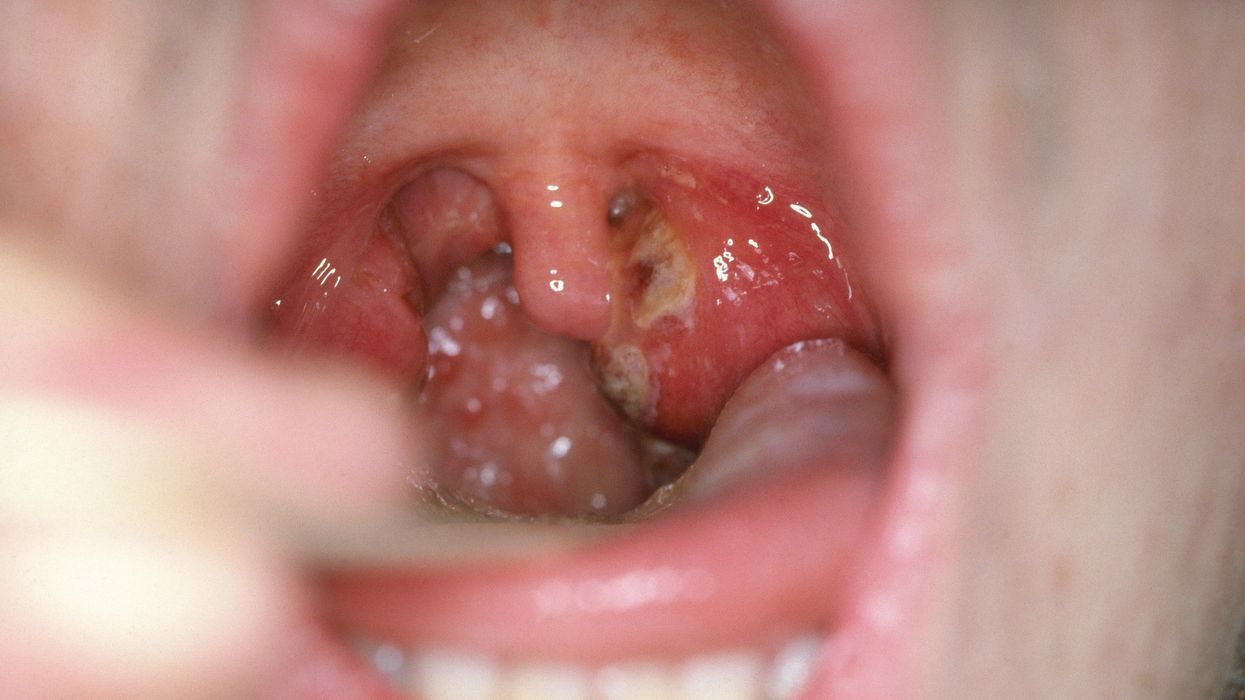

Me rastin e kontrollit, shihen të ënjtura, bajame të skuqura ndonjëherë të mbështjellë me shtresë të bardhemët e të skuqura përreth. Mirëpo, vetëm kur merret mostra më së shpeshti zbulohet shkaktari i vërtetë.

Angjina është inflamacion i bajameve të gurmazit. Shkaktar janë më së shpeshti bakteri streptokoku betahemolitik, por mund të jenë edhe viruse të ndryshme.

Dhembja e fytit, temperatura e ngritur, përpirja e vështirësuar, gjëndra të dëmtuara në qafë, janë karakteristike për angjinën.